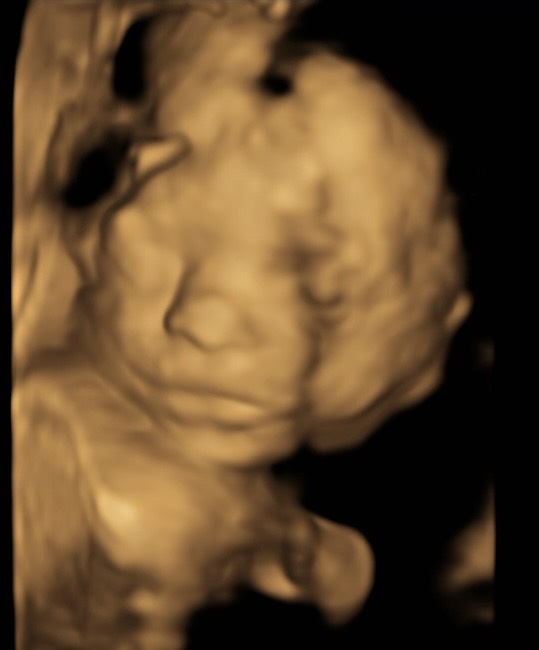

Арсений передает привет, закрывался руками, потом повернулся спиной: что это значит?

post image 3

Арсений передает привет, закрывался руками, по итогу повернулся спиной 😅